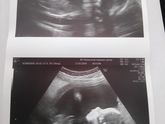

Прошёл 3 скрининг. С нашим мальчиком все хорошо. Вес 1900гр. Без патологий. Без обвития. Лежим головкой вниз. Шейка у меня 32мм. Зев сомкнут. С плацентой и водами все хорошо. Узист сказал, что дохожу до срока. Сейчас доделаем ремонт в ванной и начну … Читать далее